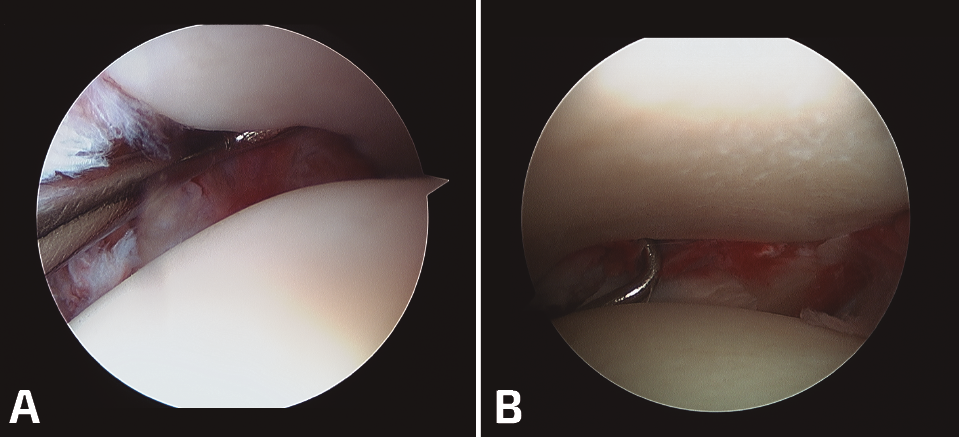

En los casos crónicos de más de 6 meses, realizaremos la artroscopia previamente a cualquier actuación. Si en la visualización articular vemos un correcto posicionamiento del peroné en su incisura y solo es un problema de estabilidad, realizaremos la misma, previo refrescado de la articulación, con sistemas de doble estabilización sindesmal e incluso plastia si lo consideramos oportuno. Siempre con visualización del estado de la articulación tibioperonea distal tras su estabilización.

En los casos crónicos, en los que la inestabilidad se asocia a desaxaciones en el plano axial, será necesario realizar osteotomías correctoras. La visión artroscópica nos ayudará a la reducción articular y estabilizaremos la sindesmosis. (Figura 4).

Figura 4. A: sindesmosis inestable; B: sindesmosis estabilizada.